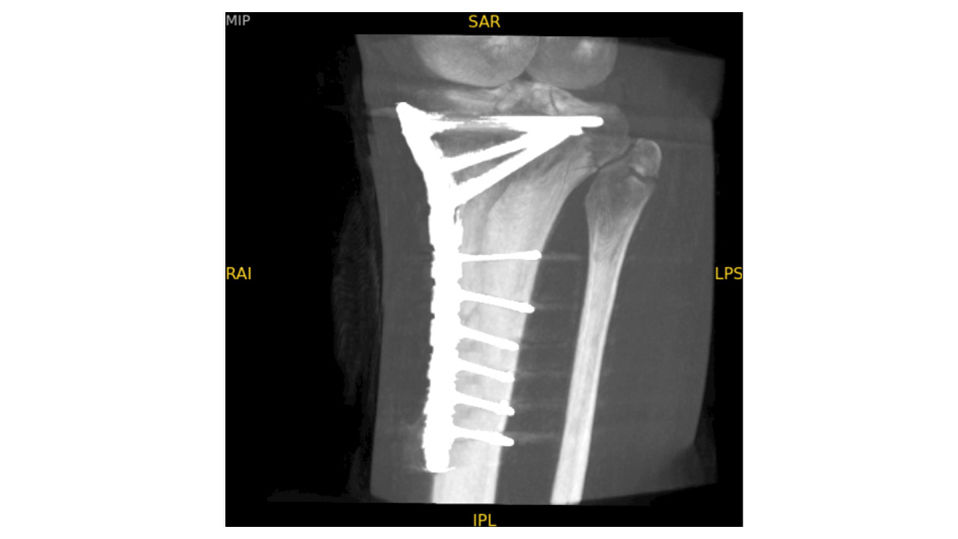

Analysieren Sie Ihre Scans mit dem GE Volume Viewer – genauso intuitiv wie am CT. Profitieren Sie von der vollständigen Darstellung axialer, koronarer und sagittaler Ebenen sowie von MIP-Ansichten und 3D-Visualisierungen im VR-Modus. Scrollen Sie durch bis zu 512 Schichten mit nahtloser Anpassung der Schichtdicke – für eine präzise Befundung direkt im OP.

oec-3d-precise-analysis-desktop